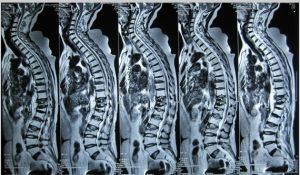

2.影像學檢查:X線檢查可確定骨折部位及類型。CT檢查判定移位骨折塊侵犯椎管程度和發現突入椎管的骨塊或椎間盤。磁共振檢查對判定脊髓損傷狀況極有價值。

本病依據其臨床表現和X線檢查,可以明確診斷,無需鑑別。但臨床上需注意骨折的發生是屬於單純性骨折還是由於患者本身原有疾疾所導致的病理性骨折,在患者原有疾病而導致骨骼異常的情況下,輕微的力量便可造成骨折,較在這種情況下發生較為頻繁,需嚴格地觀察和診斷。